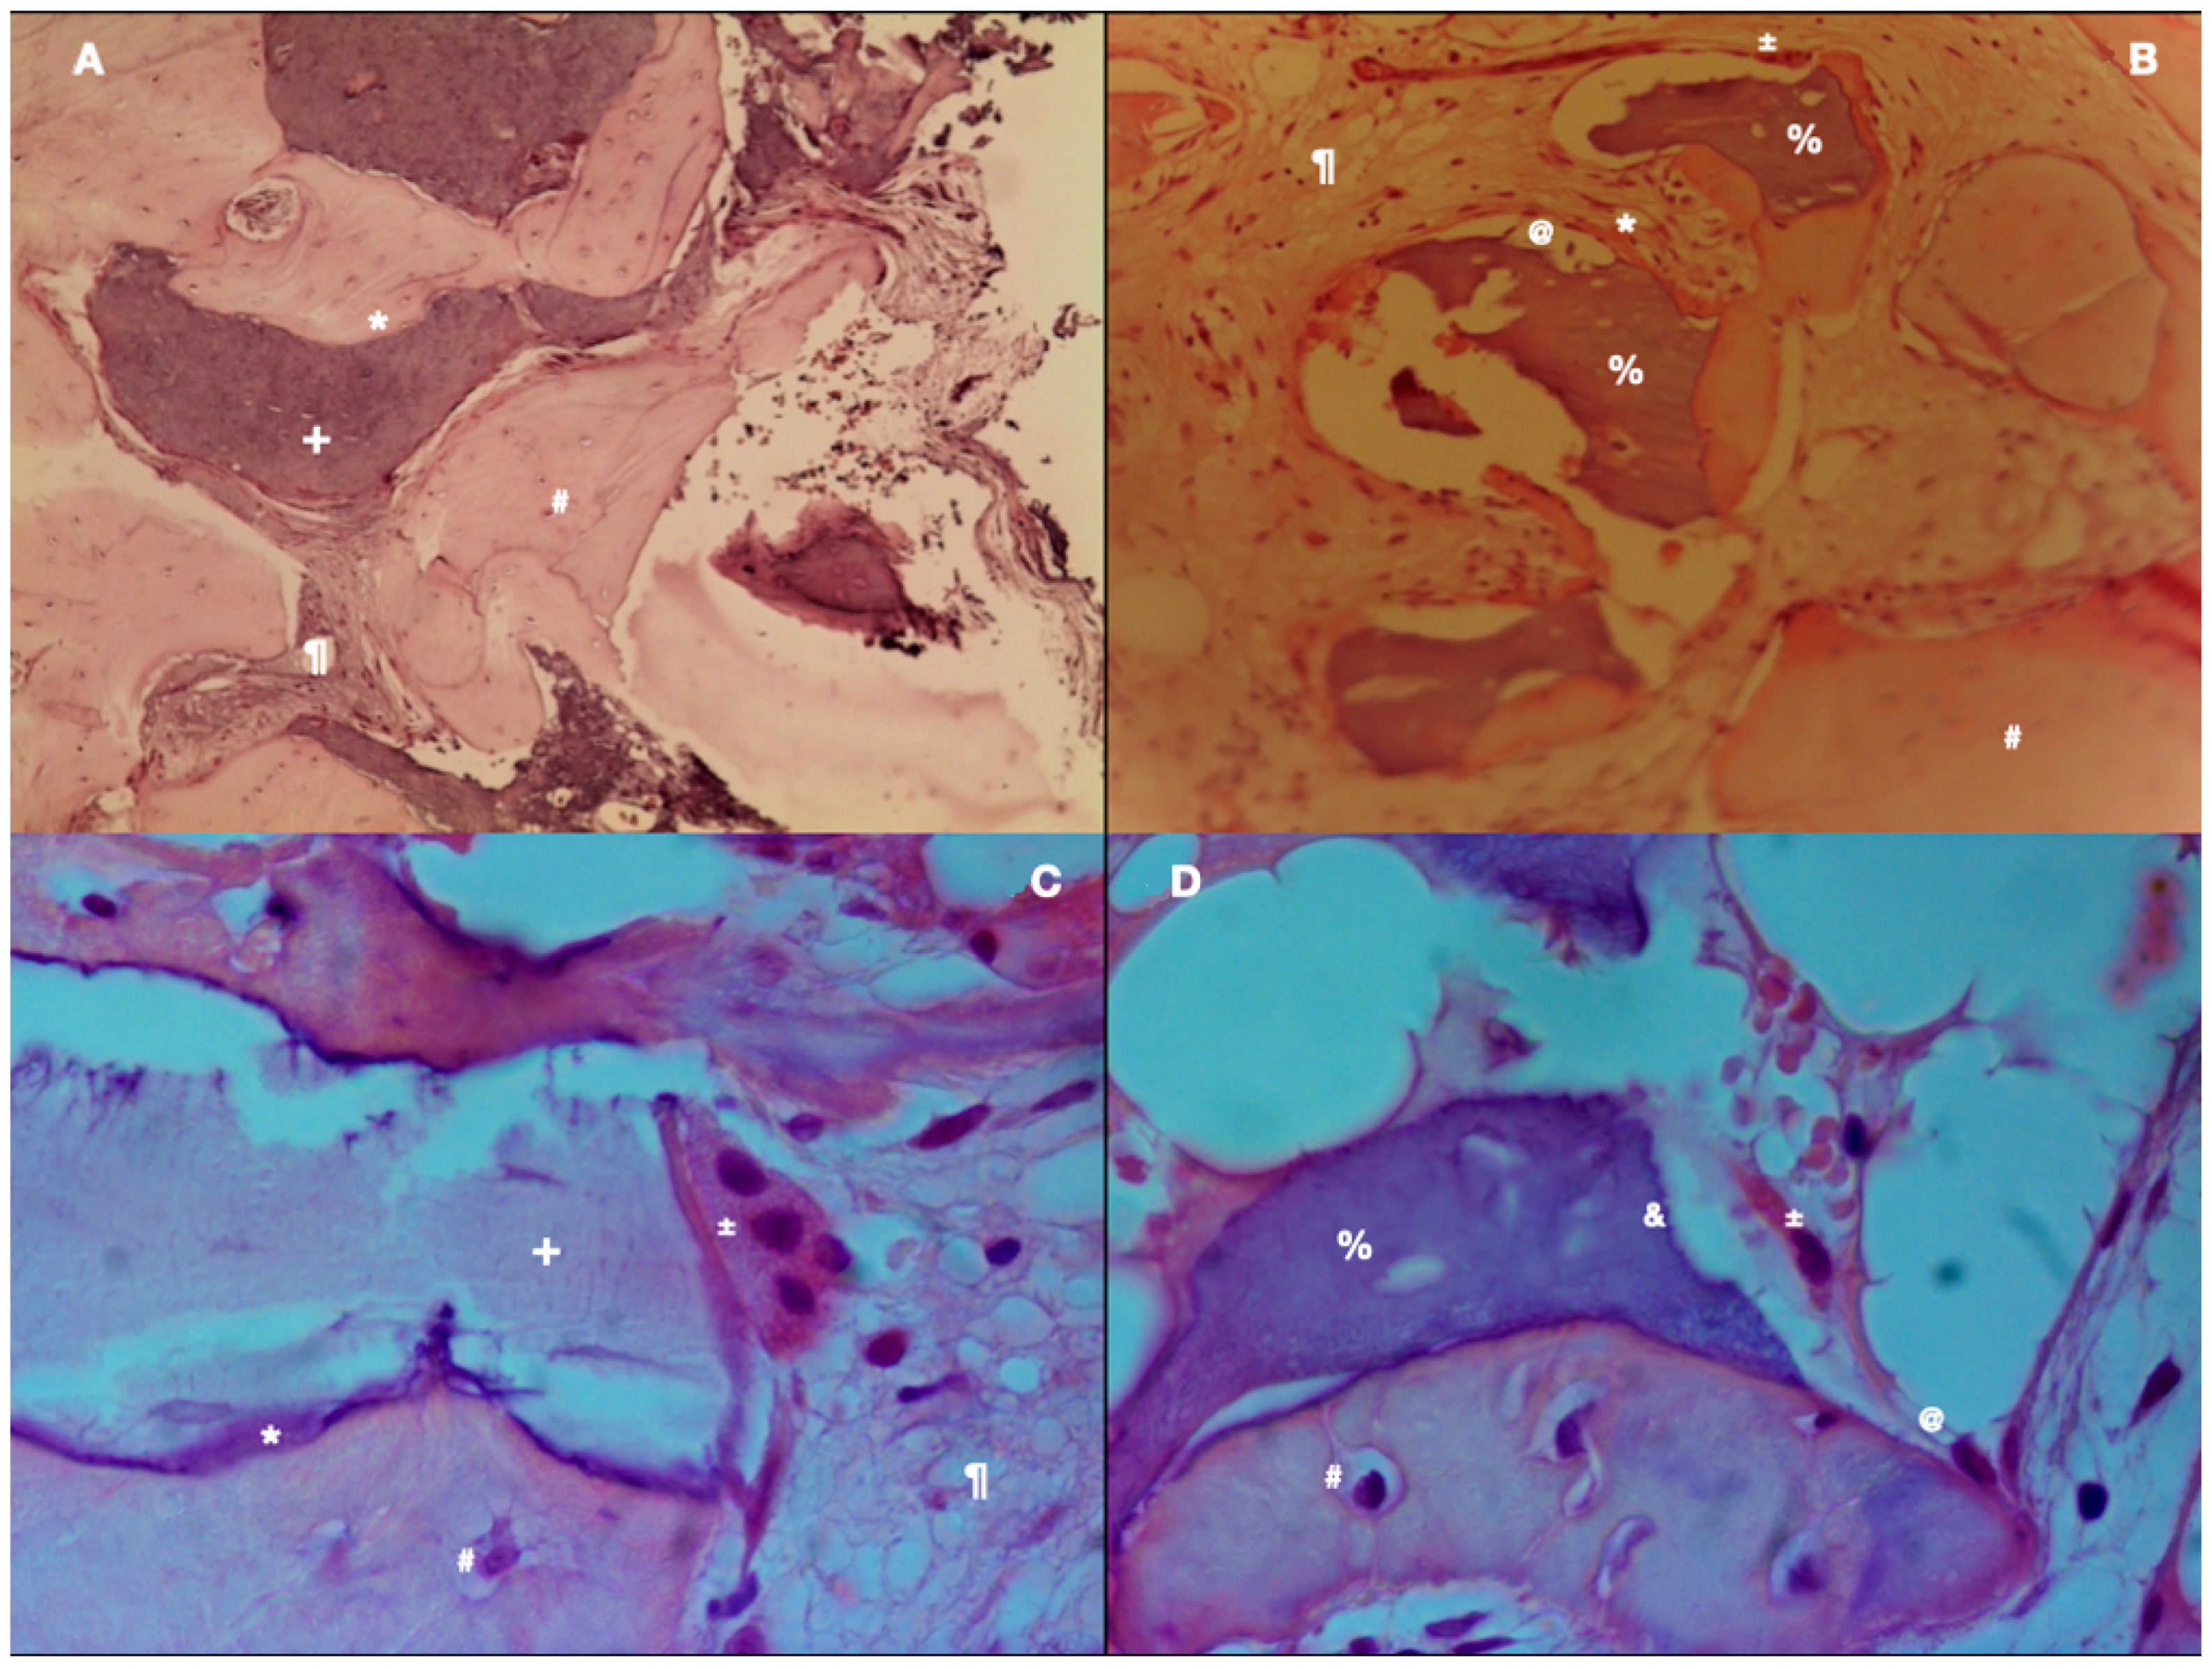

2.4. Histology Processing and Histomorphometric Analysis

3.3. Histological Findings

3.4. Histomorphometric Findings